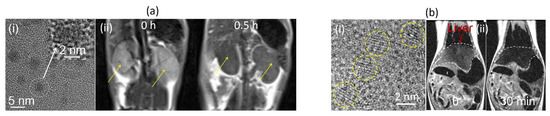

- Ahmad, M.Y.; Ahmad, M.W.; Yue, H.; Ho, S.L.; Park, J.A.; Jung, K.-H.; Cha, H.; Marasini, S.; Ghazanfari, A.; Liu, S.; et al. In Vivo Positive Magnetic Resonance Imaging Applications of Poly(methyl vinyl ether-alt-maleic acid)-coated Ultra-small Paramagnetic Gadolinium Oxide Nanoparticles. Molecules 2020, 25, 1159. [Google Scholar] [CrossRef] [PubMed]

- Dai, Y.; Wu, C.; Wang, S.; Li, Q.; Zhang, M.; Li, J.; Xu, K. Comparative study on in vivo behavior of PEGylated gadolinium oxide nanoparticles and Magnevist as MRI contrast agent. Nanomed. Nanotechnol. Biol. Med. 2018, 14, 547–555. [Google Scholar] [CrossRef]